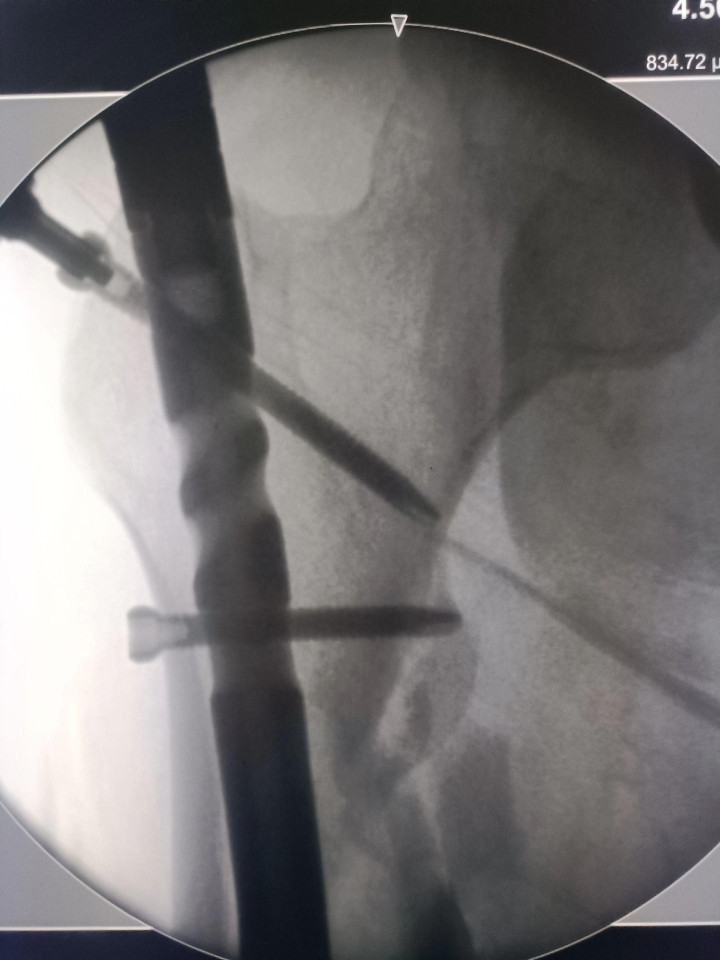

中股网 外伤导致的股骨上段骨折闭合复位股骨重建钉固定,期待早期愈合